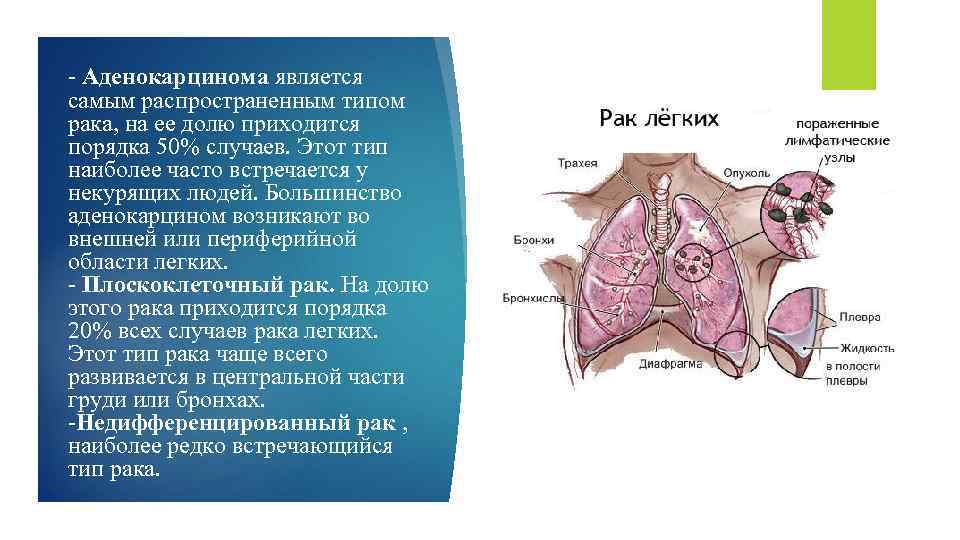

Виды рака легких: Рак легких делится на два основных вида: мелкоклеточный рак легких (МРЛ) и крупноклеточный рак легких (НМРЛ), который в свою очередь делится на:

Виды рака легких: Рак легких делится на два основных вида: мелкоклеточный рак легких (МРЛ) и крупноклеточный рак легких (НМРЛ), который в свою очередь делится на:

- Аденокарцинома является самым распространенным типом рака, на ее долю приходится порядка 50% случаев. Этот тип наиболее часто встречается у некурящих людей. Большинство аденокарцином возникают во внешней или периферийной области легких. - Плоскоклеточный рак. На долю этого рака приходится порядка 20% всех случаев рака легких. Этот тип рака чаще всего развивается в центральной части груди или бронхах. -Недифференцированный рак , наиболее редко встречающийся тип рака.

- Аденокарцинома является самым распространенным типом рака, на ее долю приходится порядка 50% случаев. Этот тип наиболее часто встречается у некурящих людей. Большинство аденокарцином возникают во внешней или периферийной области легких. - Плоскоклеточный рак. На долю этого рака приходится порядка 20% всех случаев рака легких. Этот тип рака чаще всего развивается в центральной части груди или бронхах. -Недифференцированный рак , наиболее редко встречающийся тип рака.